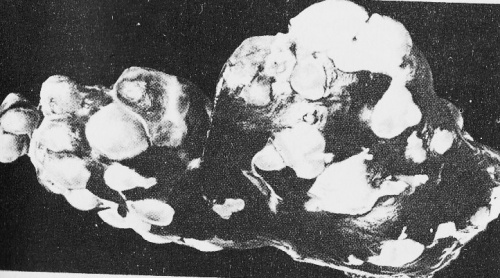

На фото: 04   Эхинококковые пузыри на печени овцы. Фото Давида Гениса.

От собак заражался скот. На печени и в легких у овец, коров тоже развиваются эхинококковые пузыри. Забил хозяин очередную овцу на бесбармак, а пузыри эти на печени или легких сразу видны, крупные, белые. Куда их? Конечно же, собакам. Я не раз фотографировал "немые" сцены: чабан свежует тушу барана, а вокруг молча сидят несколько собак и ждут, когда им перепадет их доля. В этой "доле" достаточно часто были и пораженные эхинококковыми опухолями внутренности забитых овец. Кстати, эти фото показывал чабанам. Смотрели, даже улыбались. Но потом делали то же самое...

Чтобы разобраться в том, что от чего и почему, я не раз ездил на мясокомбинат. Стоял возле ветеринаров, которые вели на конвейере экспертизу туш забиваемого скота. И забракованные органы (печень, легкие) летели в сборник отходов. Самой частой причиной и было поражение эхинококковыми пузырями. Мне важно было разобраться, насколько часто попадаются опасные, "живые" (правильнее, жизнеспособные) пузыри. И часто только удивлялся, до чего же этой "заразы" в наших овцах полно!

Если попадался единичный пузырь, контролер его просто вырезал, остальной продукт отправлялся дальше по конвейеру. Чаще печень или легкие были просто усыпаны разными по размеру белыми пузырями. По моим подсчетам, до 50-80 процентов всех случаев поражения были множественными, а в трети всех случаев до того было напичкано этих кист, что почти не видна была ткань печени или легкого.

Часть пузырей мы собирали и уже у себя в препараторской я их вскрывал. Так я просмотрел 163 пузыря от овец и только в трех из них не обнаружил зародышевых головок. Для сравнения я присутствовал при экспертизе туш крупного рогатого скота и тоже часть собранных пузырей вскрывал. Тут была совсем другая картина. И пузырей было меньше, и жизнеспособными из них были чуть ли не единичные. Отсюда следовал логичный вывод - в наших условиях главную роль играли овцы. Это они, важное звено, поддерживали очаги эхинококкоза.

Если же учесть, что приходилось много объяснять, выступать, предлагать на всех уровнях, от чабанов до высокого начальства, то наши "родные" цифры и данные звучали неплохим "музыкальным" сопровождением. Одно дело было сказать, что овцы виновны, а другое, когда показывал фотографии и раскладывал цифры. Как в судебном процессе: "вещдок" в роли главного аргумента...